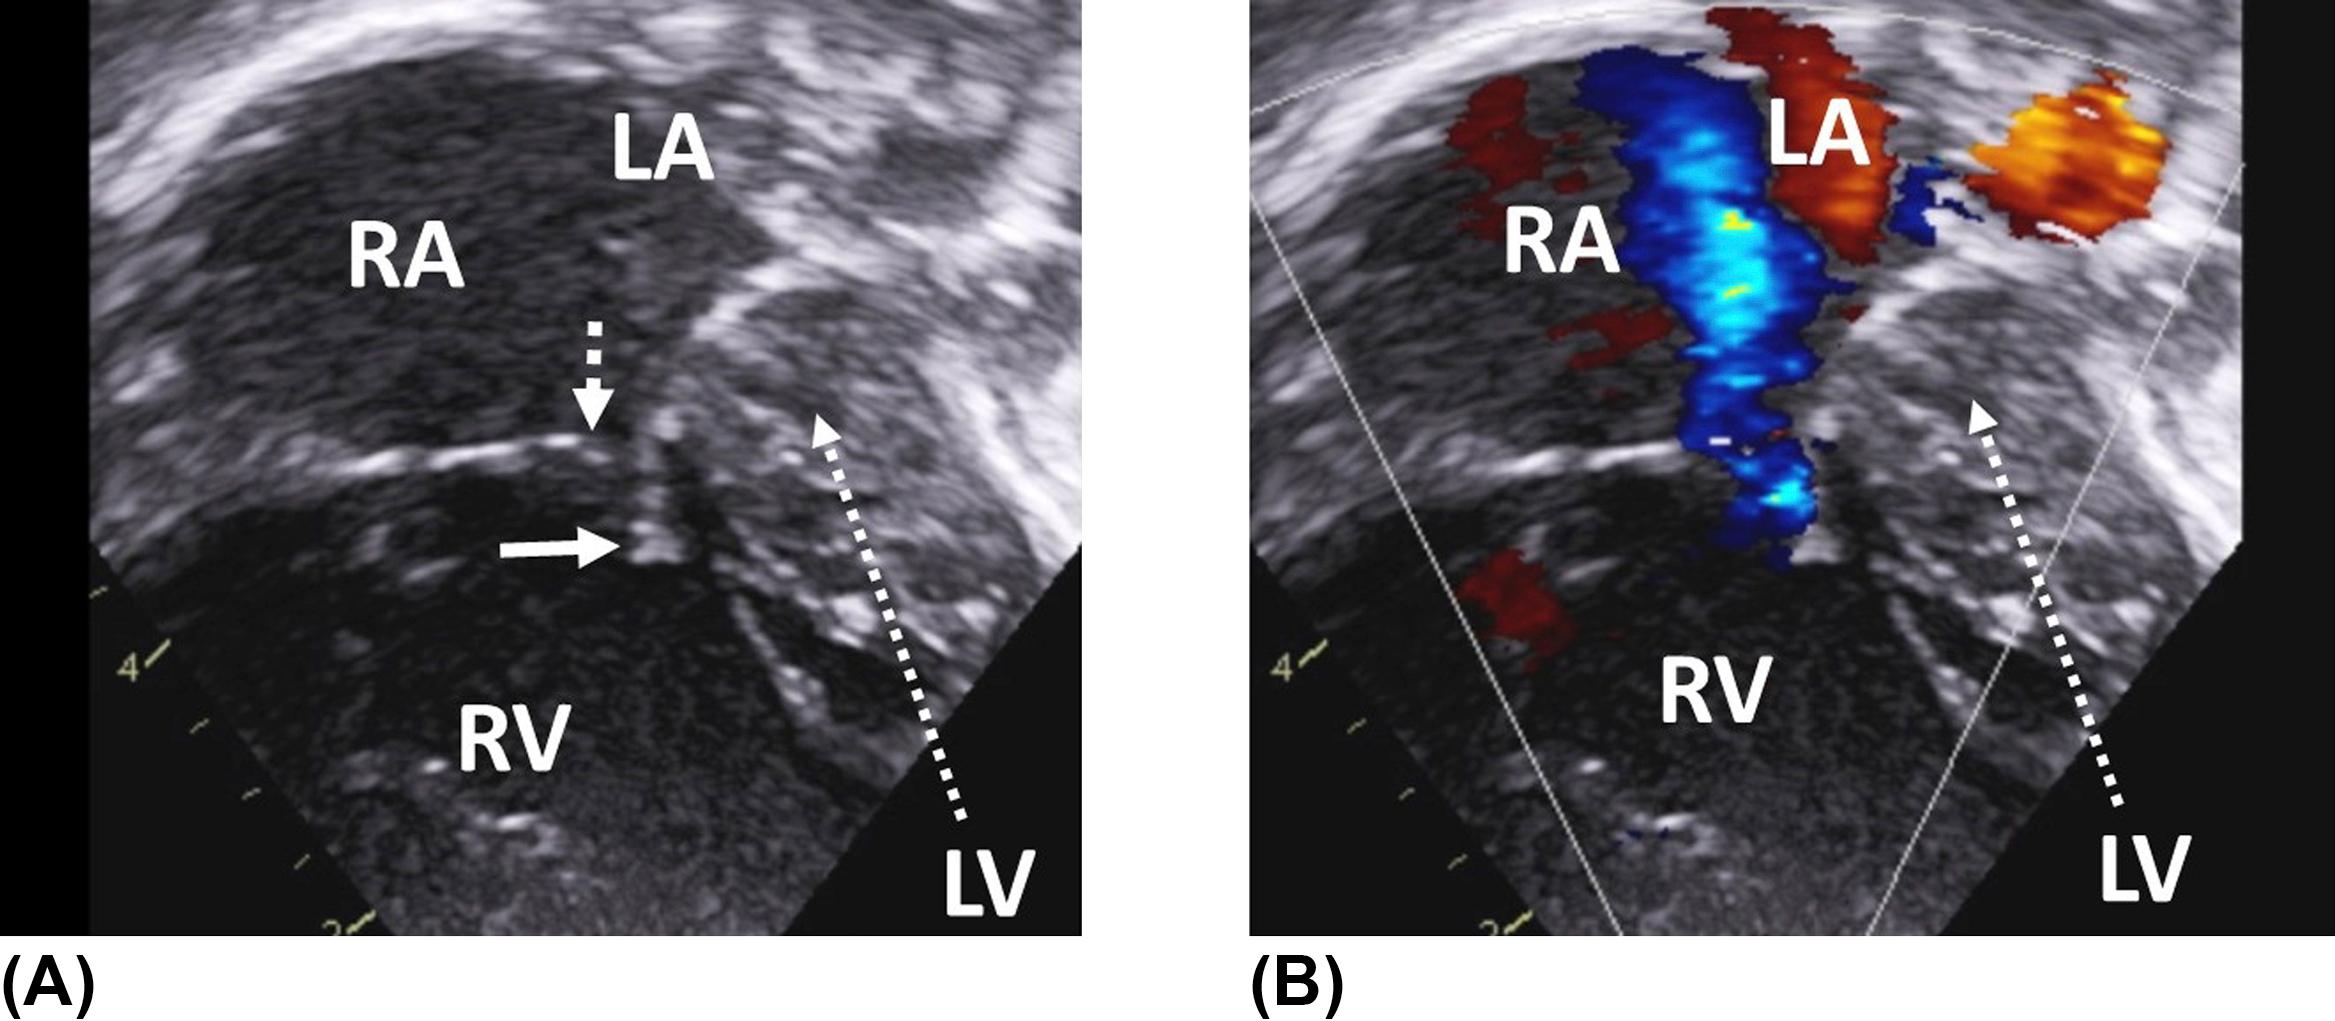

Figure 3, Apical four-chamber view in a child with severe hypoplasia of the left ventricle. There is detectable flow across the very stenotic mitral valve ( arrow ) on color flow mapping. Note the right atrial and ventricular dilatation. LA , left atrium; LV , left ventricle; RA , right atrium; RV , right ventricle.

Figure 4, (A) Apical four-chamber view in a newborn with hypoplastic left heart syndrome and a very diminutive left ventricle. Note the incomplete coaptation between the anterior and septal leaflets of the tricuspid valve caused by the reduced motion of the fixed septal leaflet. Dotted arrow indicates the tip of the antero-superior tricuspid valve leaflet, plain arrow the tip of the septal tricuspid valve leaflet. (B) As a consequence, there is severe tricuspid regurgitation contributing to the dilatation of the right-sided chambers. LA , left atrium; LV , left ventricle; RA , right atrium; RV , right ventricle.